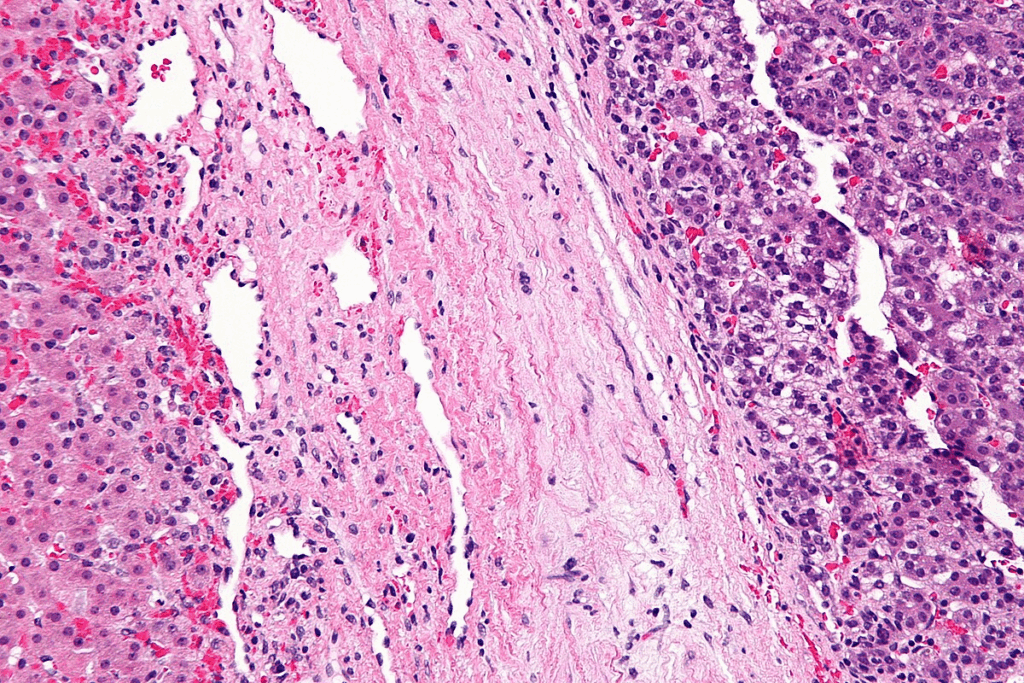

Histological Subtypes

Hepatoblastoma can be divided into different types based on how the tumor cells look under a microscope. The main types are epithelial and mixed. Some research suggests that certain types might have different chances of recovery, but more study is needed.